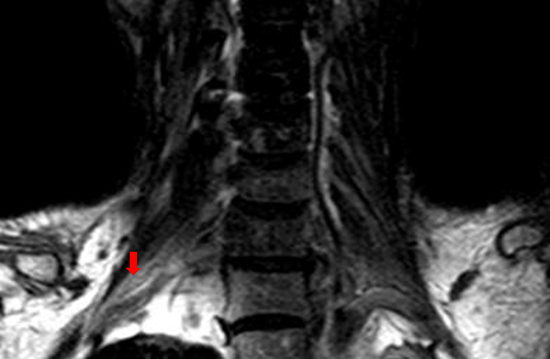

MRI of brachial plexus excluded tumor relapse in all the patients. Short tau inversion recovery (STIR) showed asymmetrical polyradiculopathy identified by unilateral or bilateral swollen in cervical roots extending through to the trunks. These abnormalities are common in C-5~C-8 levels but rare in the first thoracic vertebrae level (T-1). The injured nerves showed hyper-intensity on T1 and T2 weighted MRI images (Figure 4, Figure 5). The lesions of 8 patients showed enhancement at enhanced T1-weighted image (Figure 5C). Diffusion weighted MR imaging showed high intensity in the affected brachial plexus, indicating nerve edema (Figure 5D). Adjacent tissue surrounding the plexus was usually normal and intact.

Figure 4: The T1-weighted coronal MRI scan of one case with unilateral RIBP. The MR imaging showed high intensity within the left brachial plexus (red arrow), compared with the normal right brachial plexus.